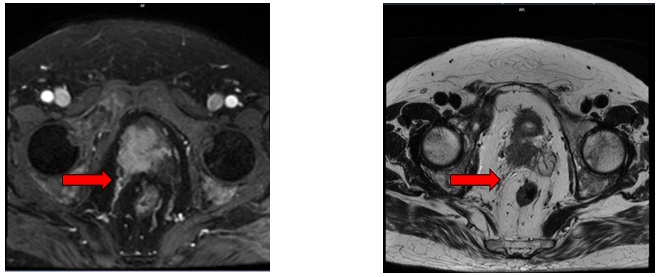

- Chụp cộng hưởng từ tiểu khung: (14/03/2025)

+ Hình ảnh u tuyến tiền liệt kích thước 30x40mm, xâm lấn túi tinh phải.

+ Các ổ tổn thương xương cùng, xương chậu, cổ xương đùi 2 bên, hạch cạnh bó mạch chậu bên phải kích thước 31x22mm - Theo dõi thứ phát

Hình 1. Hình ảnh chụp cộng hưởng từ tiểu khung: Hình ảnh u tuyến tiền liệt kích thước 30x40mm, xâm lấn túi tinh phải (mũi tên màu đỏ)